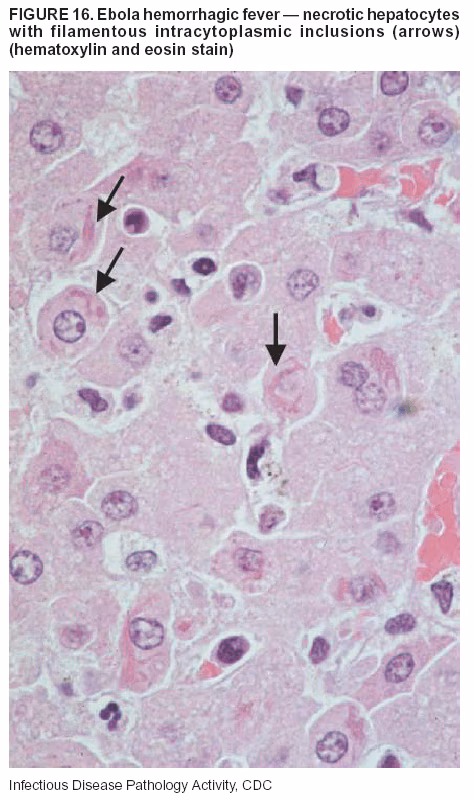

Pathologic Findings. The term viral hemorrhagic fever is reserved for febrile illnesses associated with abnormal vascular regulation and vascular damage. Common pathologic findings at autopsy include petechial hemorrhages and ecchymoses of skin (Figure 15), mucous membranes, and internal organs. Although systemic hemorrhages occur in the majority of viral hemorrhagic fevers, certain agents infect specific cells and thus histopathologic features can differ among agents. Necrosis of liver and lymphoid tissues, as well as diffuse alveolar damage, occur in the majority of viral hemorrhagic fevers, but can be more prominent for certain infections (e.g., midzonal hepatocellular necrosis is prominent in yellow fever, but not in dengue). Viral inclusions can be visualized in hepatocytes with Ebola or Marburg infections by using light and electron microscopy (Figure 16) (49--54).